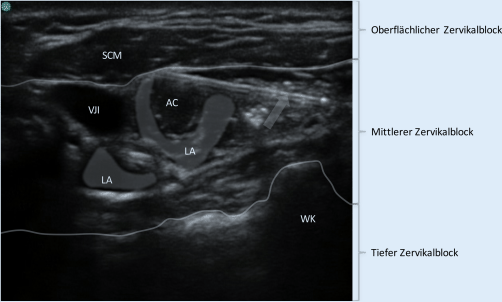

Abb. 2

Ultraschallbild der Halsregion rechts. Eingezeichnet sind die verschiedenen anatomischen Ebenen, welche dem oberflächlichen, mittleren und tiefen Zervikalblock entsprechen. Die anatomischen Grenzen wurden jeweils durch die grauen Linien markiert. Der Pfeil markiert die mit dargestellte Nadel. Im konkreten Fall handelt es sich um einen mittleren Zervikalblock. Das Lokalanästhetikum bildet ein Depot sehr tief im Bereich des Plexus (hier dargestellt unter der V. jugularis), sowie ein zweites die A. carotis umspülend (innerhalb der Karotisfaszie). WK Wirbelkörper, LA Depots eingebrachten Lokalanästhetikums, VJI Vena jugularis interna, SCM Musculus sternocleidomastoideus